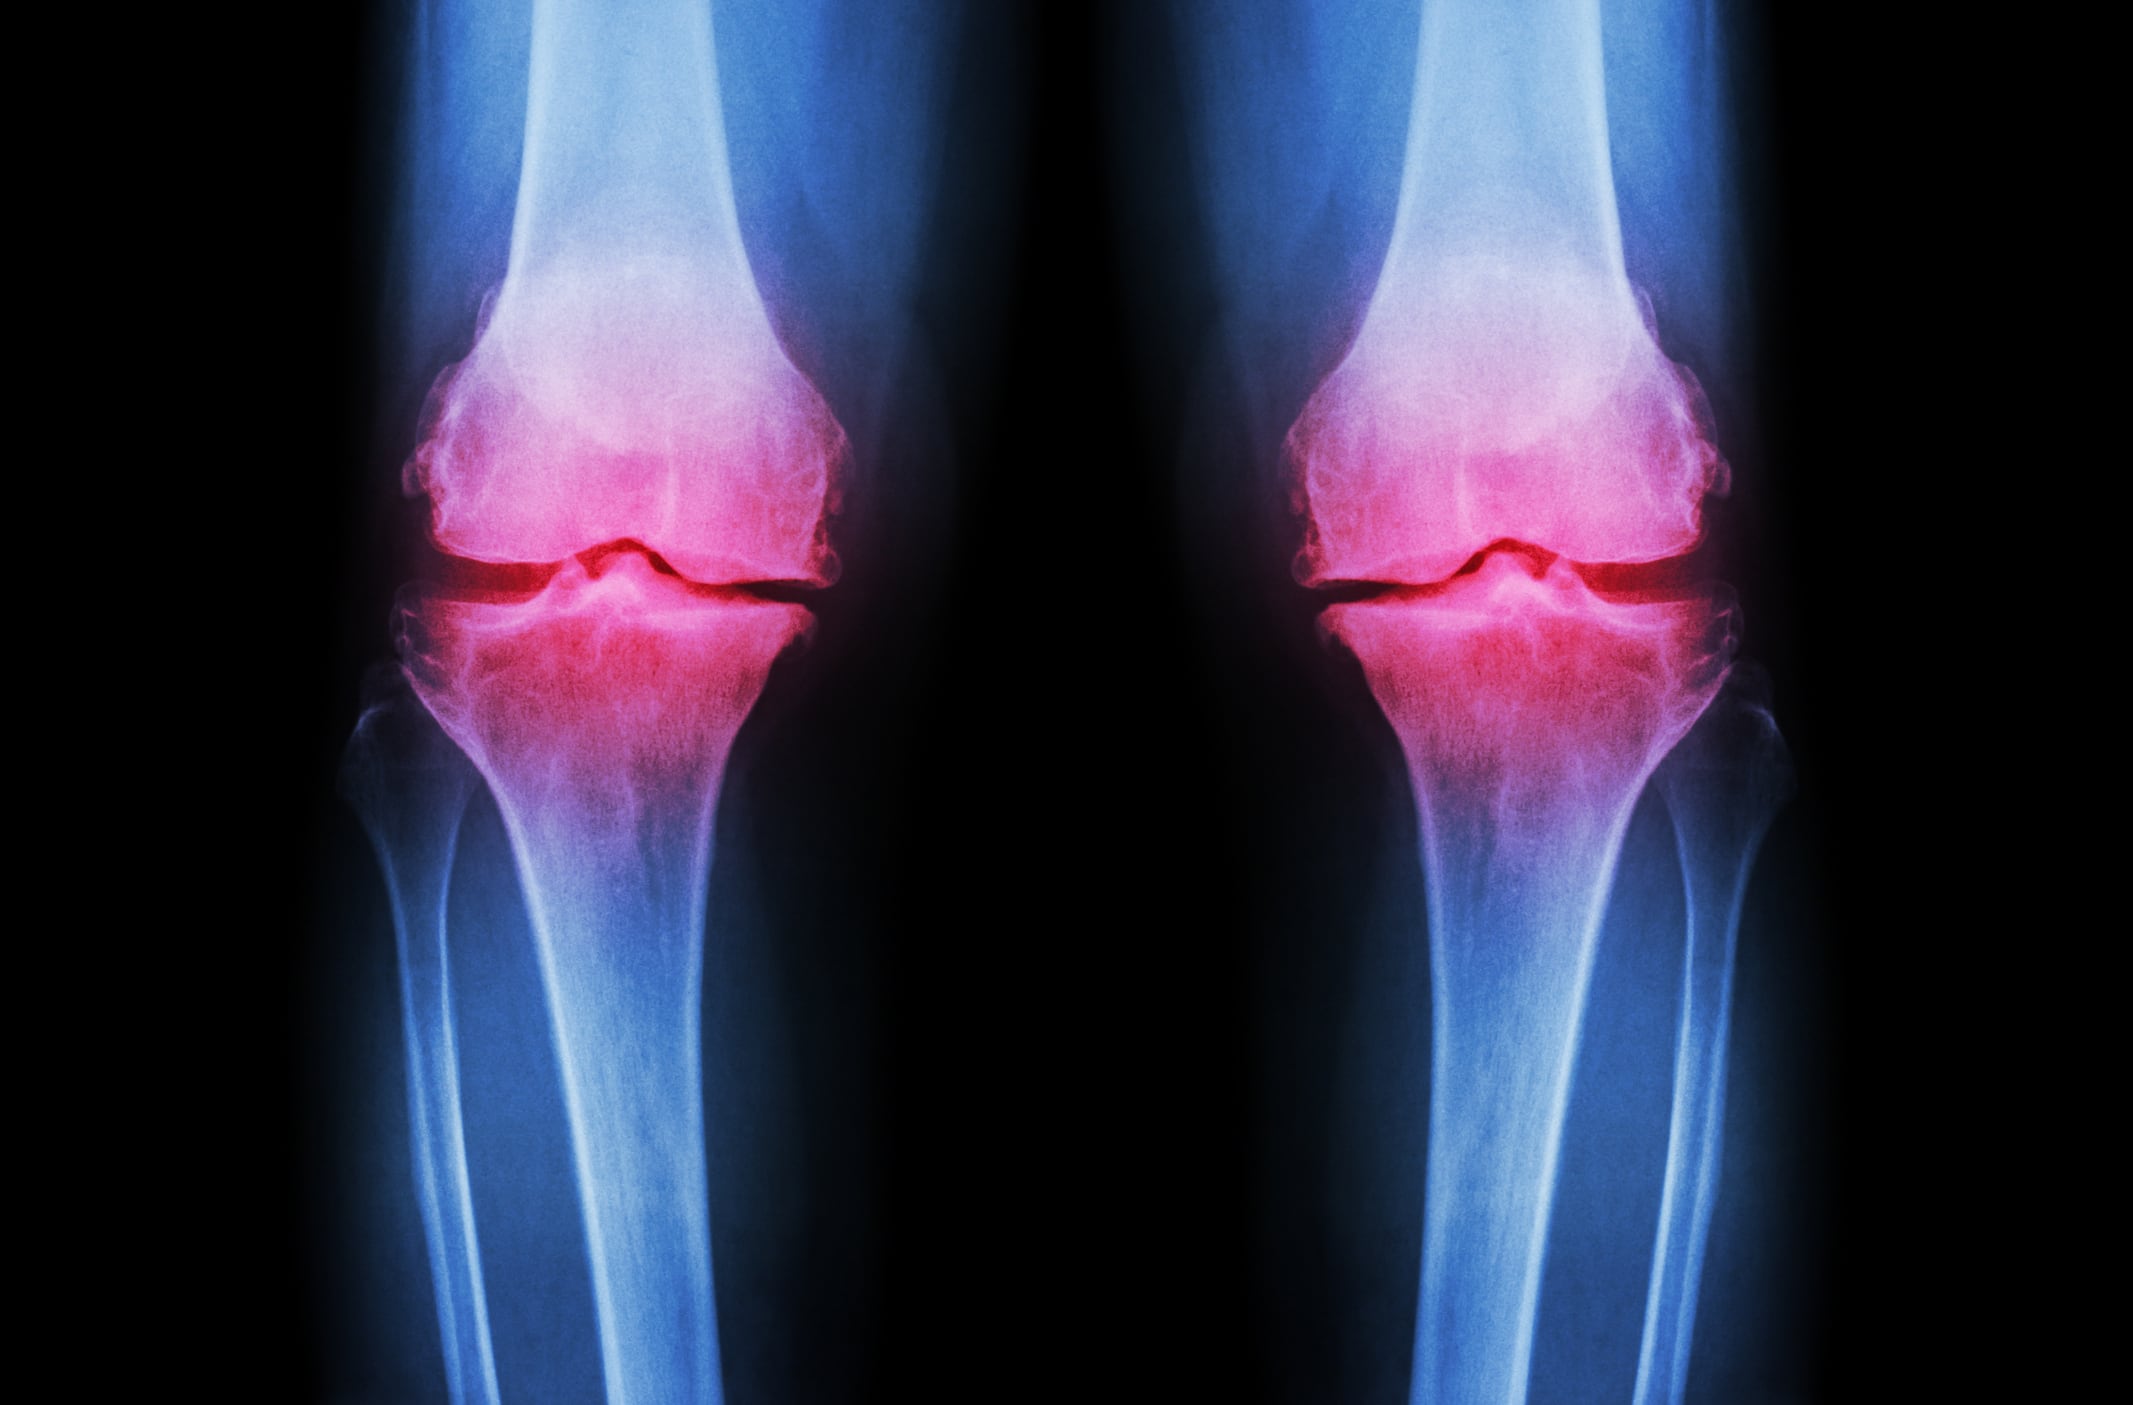

Data from randomized placebo-controlled trials of collagen showed that supplements showed a significant reduction in the score of total Western Ontario and McMaster Universities Osteoarthritis index (WOMAC), compared to placebo.

Additional analysis of WOMAC subscores indicated that collagen supplementation was associated with significant decreases in stiffness, compared to placebo.

On the other hand, no significant impacts were found for pain or functional limitation, wrotesScientists from the Universidad Autónoma de Nuevo León in Monterrey and the Mexican Social Security Institute in Durango in the journal International Orthopaedics.

Collagen supplementation was also associated with significant reductions in scores on the visual analog scale (VAS), they wrote.

“The results of this meta-analysis showed that collagen is effective in improving [osteoarthritis] symptoms by the decrease of both total WOMAC index and VAS score,” they concluded.